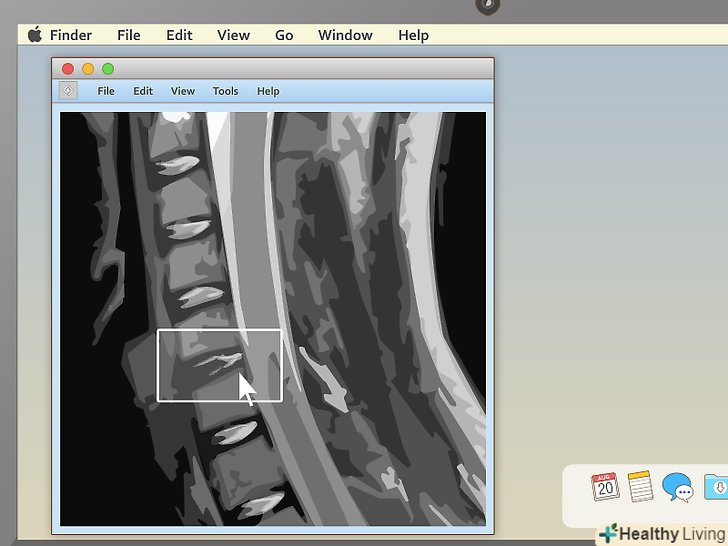

Вивчіть структуру хребців, якщо ви розглядаєте МРТ хребта.МРТ хребта прочитати чи не найпростіше іншого (особливо в саггитальной проекції). Пошукайте порушення в розташуванні хребців або міжхребцевих дисків. Якщо хоча б один буде не не своєму місці (як в прикладі вище), це може стати джерелом сильного болю.- За хребтом у саггітальній проекції ви побачите щось біле, схоже на мотузку. Це спинний мозок, який пов'язаний з усіма нервовими закінченнями в організмі. Пошукайте ділянки, де хребці або диски притискають спинний мозок. Оскільки нервові закінчення дуже чутливі, навіть невеликий тиск призводить до болю.